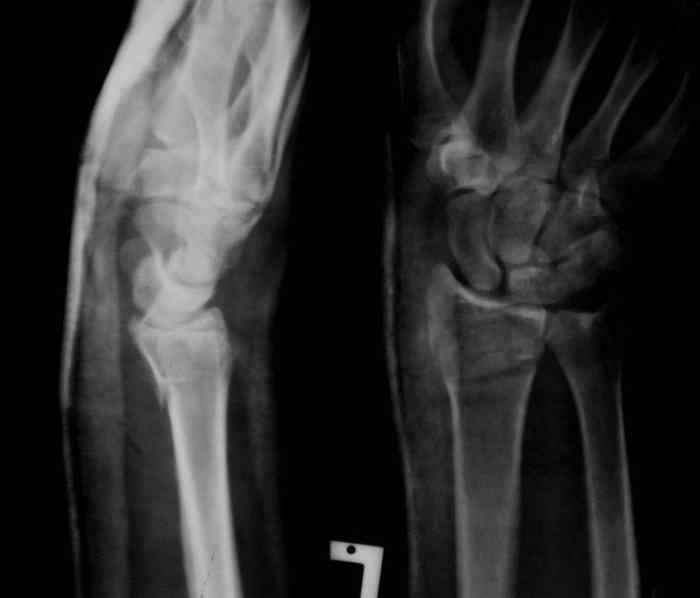

Под проводниковой анестезией произвел аккуратную одномоментную репозицию, фиксацию гипсовой повязкой в положении умеренной экстензии. Думаю неплохо получилось. Мягкие ткани не вызывали опасений в плане Зудека.

13.12.2007.jpg

37KB (38539 bytes)